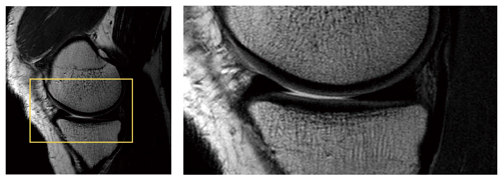

図6は,膝関節の高空間分解能画像です。関節の診断に重要な関節液が半月板とともに明瞭に描出されており,また,骨髄や皮質,軟骨などの層構造が観察できます。

図6 3T MRI画像例:膝関節,FSE PDWI(1024マトリックス)